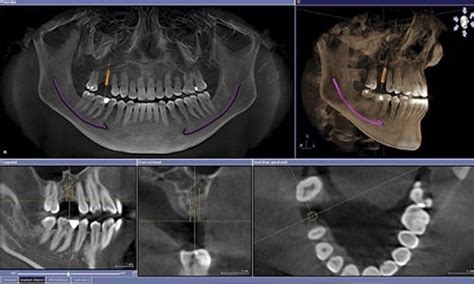

La radiografía TAC dental 3D es una prueba radiológica moderna utilizada en odontología para obtener imágenes precisas y detalladas de la estructura ósea de la mandíbula y el maxilar. Este tipo de estudio es esencial para una variedad de tratamientos y diagnósticos dentales.

- Colocación de implantes dentales: Permite determinar si la mandíbula cuenta con la cantidad y densidad suficiente de hueso para dar soporte al implante y encontrar la mejor posición para colocarlo.

- Reendodoncias: Permite visualizar la imagen tridimensional de las raíces para determinar si es posible realizar una reendodoncia.